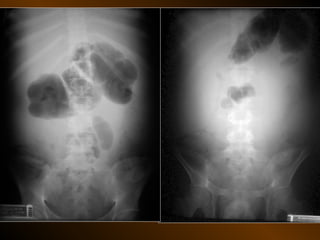

• Căng giãn ruột non

• Căng giãn đại tràng

PHÂN BIỆT

RUỘT NON – ĐẠI TRÀNG

• Các nếp Kerckring

• Nếp ngấn thanh mạc

• Khẩu kính

• Số lượng quai

• Phân bố các quai ruột

• Cao / rộng

• Chất cặn bã